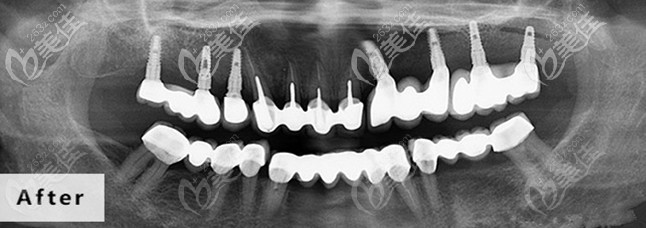

德道口腔设有种植科、正畸、修复科、综合治疗科、洁牙保健科、儿童牙科等诊疗室,每个科室都有专科医生坐诊,配置进口的全景仪、牙椅、消毒、技工等牙科治疗设备。

即刻用3.0种牙技术:帮您当天戴牙冠,完成种植牙手术,更节约时间。